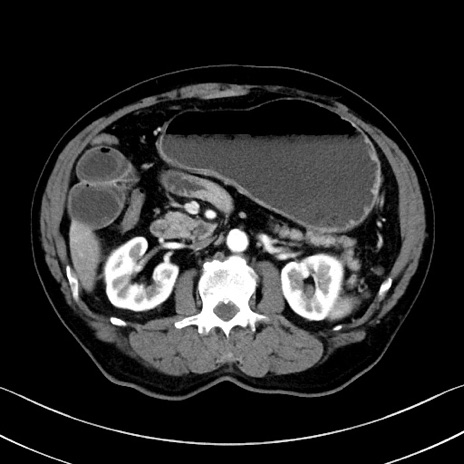

冠状断像

症例35(横断像)

【症例】70歳代 男性

【主訴】腹部膨満、嘔吐

【現病歴】昨日より腹部膨満感出現。本日増悪し、仙痛出現。嘔吐あり、受診。

【既往歴】糖尿病、胆摘後

【身体所見】BP 149/80mmHg、HR 74/min、BT 35.9℃、腹部:膨満、軟、圧痛なし。腸雑音減弱あり。上腹部正中切開瘢痕あり。

【データ】WBC 13500、CRP 1.72